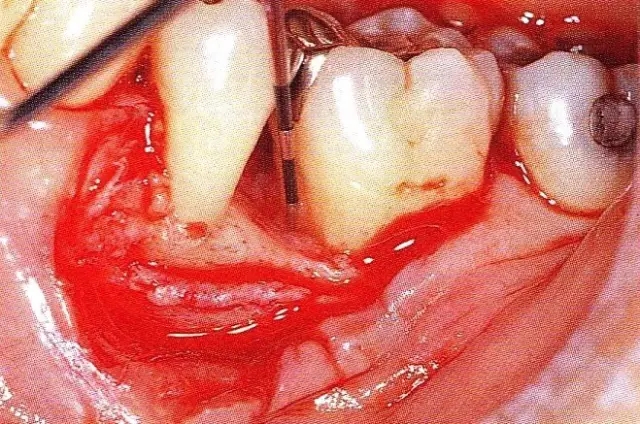

▲圖7-1  左下6近中可觀察到3壁性垂直性骨缺損。此病例考慮到齦瓣供血關(guān)系,在前磨牙部位進(jìn)行了減張切開,沒有進(jìn)行縱切開。并利用刮治器、牙周外科用車針進(jìn)行了徹底的骨缺損部位搔刮。